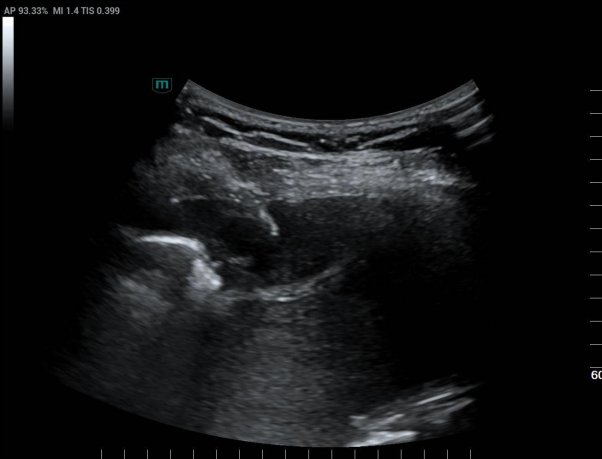

超声医学科主任潘国栋与主治医师刘金昊依据超声显示的病变范围,细致规划了穿刺点、进针路线及深度,避开了肋间动脉、神经及病变侧方的肺组织。全程在超声的实时引导下,穿刺针精准到达病变部位,采集了2条病变组织。

经超声引导下避开血管、实时显示穿刺针从进入胸膜结节到击发穿刺针的全过程